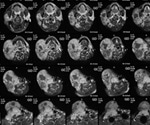

Gadolinium Deposition in the Brain